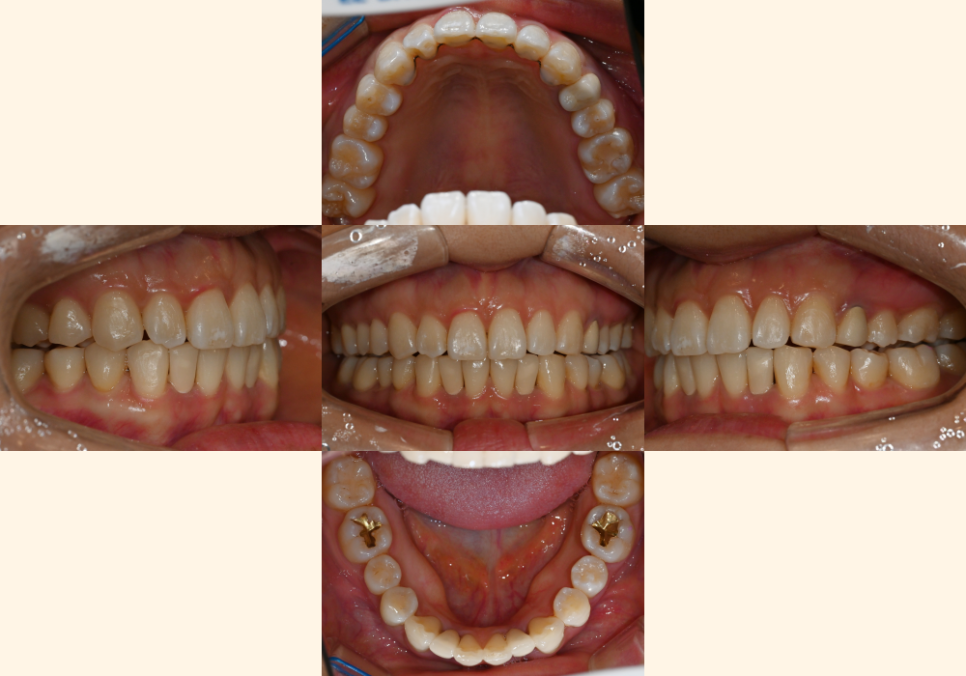

위 사진을 보면

전체적으로 치열이 틀어져 있는 것을

확인할 수 잇었으며

결손된 부위로 인해

아랫니가 벌어져 있는 것을

확인할 수 있습니다.

양쪽 교합을 확인해 보면

왼쪽 어금니 부위가

반대교합이 확인됩니다.

윗니는 삐뚤빼뚤하며

위 앞니가 아랫니를 덮는 양이 부족합니다.

교합면을 보았을 땐

아래 앞니 2개가 결손되어 있으며

사이 공간이 있습니다.

위아래 앞니 사이 거리가 과도합니다.